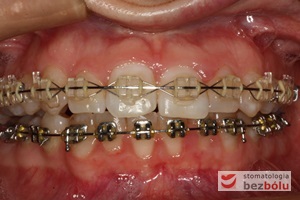

Pacjentka lat 22 zgłosiła się do naszej placówki celem podjęcia leczenia ortodontycznego. Głównym oczekiwaniem pacjentki była poprawa estetyki uśmiechu oraz brak ekstrakcji zębów na drodze do jej uzyskania. Ze względu na liczne stłoczenia zębów w górnym i dolnym łuku, dość duży materiał zębowy w porównaniu z bazą kostną, a także zgryz przewieszony boczny prawostronny po dokładnej analizie cefalometrycznej oraz analizie modeli diagnostycznych zastosowano leczenie bezekstrakcyjne z wykorzystaniem strippingu jako alternatywy dla usuwania zębów, mającego na celu uzyskanie miejsca w łuku na uszeregowanie zębów. Po fazie aktywnego leczenia trwającego 18 miesięcy zastosowano leczenie retencyjne w postaci szyny retencyjnej w łuku górnym oraz retainera stałego w łuku zębowym dolnym klejonego od kła do kła.